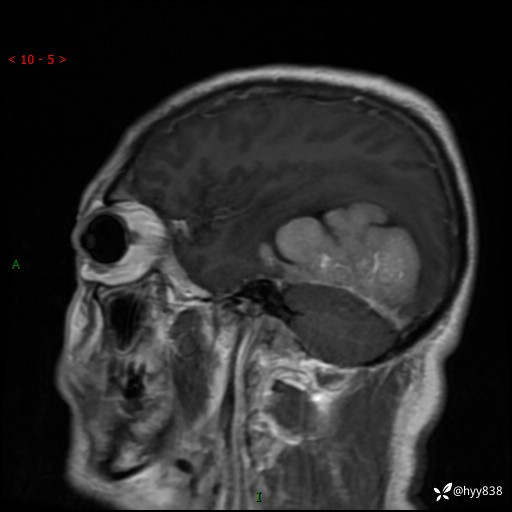

患者性别:男

患者年龄:56岁

简要病史:外院CT提示脑膜瘤,为进一步诊治来我院

辅助检查:MRI

临床诊断:颅脑占位

颅脑MRI平扫+增强